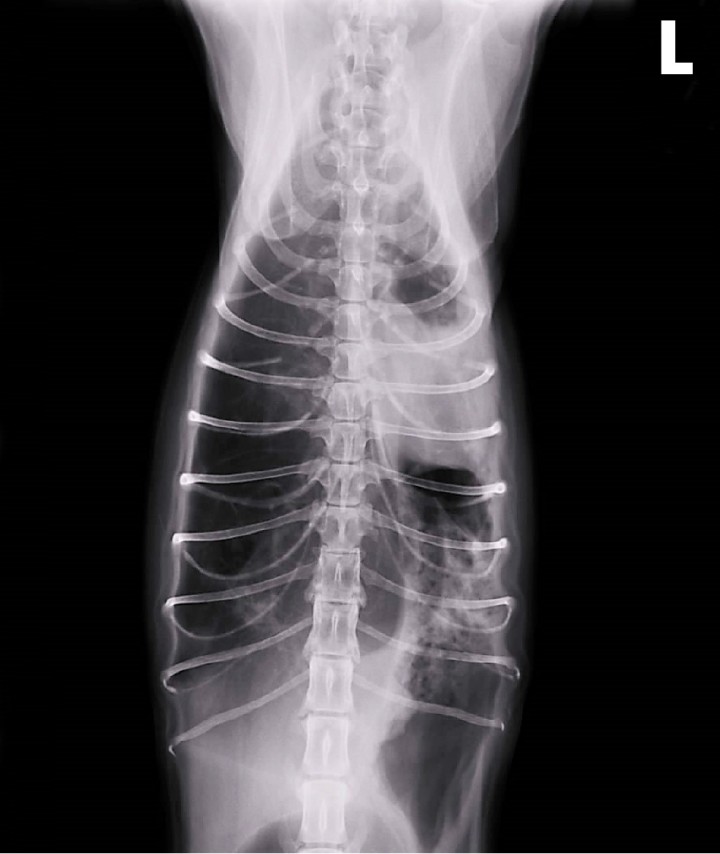

Se realiza radiografía torácica dorsoventral (Fig. 3), en la que se observa el pulmón derecho hiperinsuflado, con desplazamiento lateral del corazón hacia el lado izquierdo. El pulmón izquierdo presenta marcada reducción de volumen por hipoinsuflado, con presencia de alveogramas, regiones atelectásicas y una aparente bulla. Ante estos hallazgos y la pobre respuesta al tratamiento médico, se propone la realización de más pruebas diagnósticas, como una Tomografía Computarizada (TC) de tórax y/o toracotomía exploratoria. Ante la alta probabilidad de requerir un tratamiento quirúrgico posterior, los propietarios deciden realizar la toracotomía exploratoria por ser un método que permite simultáneamente implementar medidas diagnósticas y terapéuticas.

<p>Radiografía de tórax dorsoventral. Desviación del corazón hacia lado izquierdo del tórax por atelectasia completa de pulmón izquierdo, que presenta patrón intersticial-alveolar y una posible bulla enfisematosa en polo caudal. Pulmón derecho hiperinsuflado. L: izquierda.</p>

Radiografía de tórax dorsoventral. Desviación del corazón hacia lado izquierdo del tórax por atelectasia completa de pulmón izquierdo, que presenta patrón intersticial-alveolar y una posible bulla enfisematosa en polo caudal. Pulmón derecho hiperinsuflado. L: izquierda.